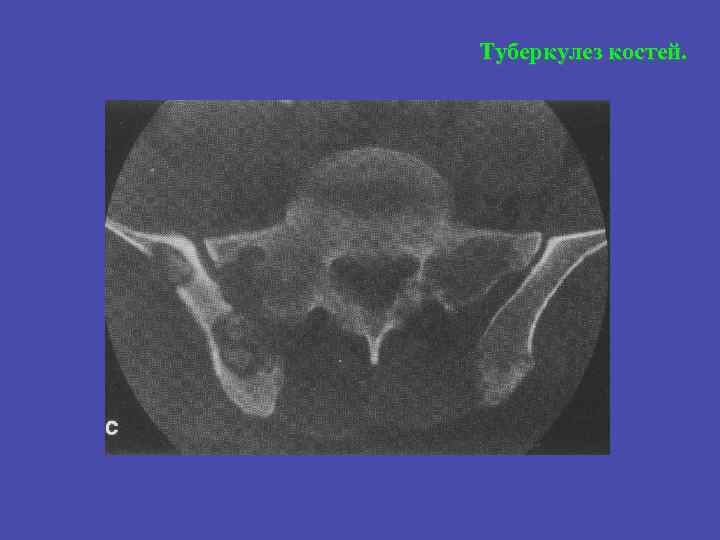

Туберкулез костей.